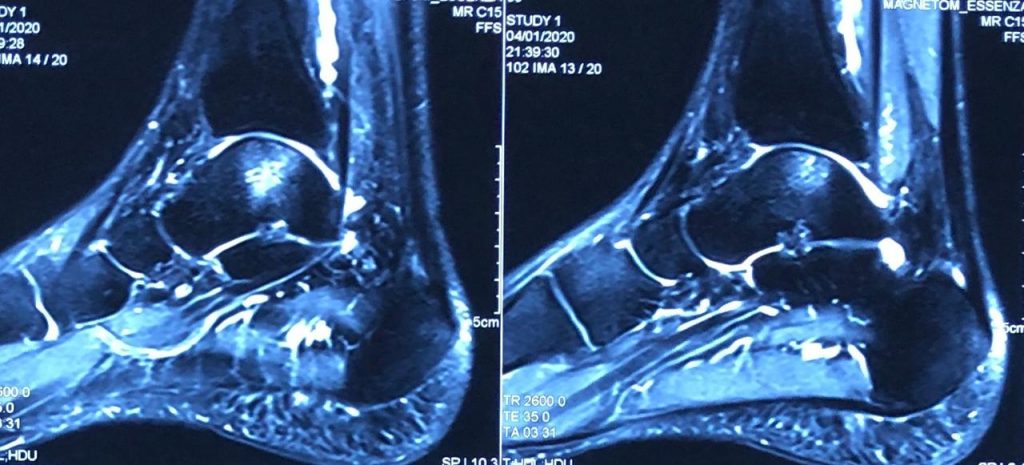

He was thoroughly examined with an MRI scan of ankle, which showed a defect in cartilage of around 18 mm x 20 mm over the left talar dome in the weight bearing axis. This was the real reason for his pain. He couldn’t remember the exact reason for the injury too. Later he doubted about the ankle injury which he met with long ago.